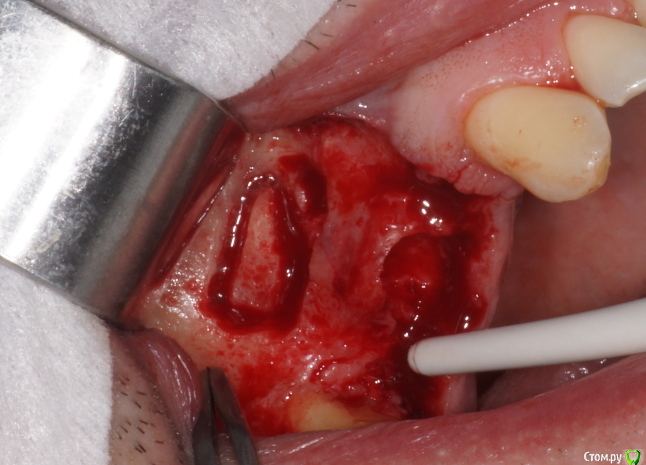

В день вмешательства обрадовала ассистент - оказывается заказ "открытый синус лифт" еще не предполагает заказа на комплект гладилок. Сетевые клиники такие сетевые. Пришлось дедовским способом - турбинка, серповидная и распатор.

В начале планировал три имплантата, между зубами - 18,5 мм, в притык. Когда делал анестезию посмотрел наконец-то в рот (не смейтесь, внимательно посмотрел) - подумал, что моляр и два премоляра ортопед может не всунуть. Короче, передумал и решил ставить два и если че - пусть мостик или консоль делает.

За качество некоторых фото прошу прощения, что мог делал сам, но в гуще событий доверил камеру второму ассистенту. Уговорить человека не прожимать спуск без задержки на автофокус не удалось, как и заставить приблизиться ближе чем на метр. Радует что когда закупался то выбрал макросотку - на 60мм которую мне предлагали вообще нифига не видно было бы.